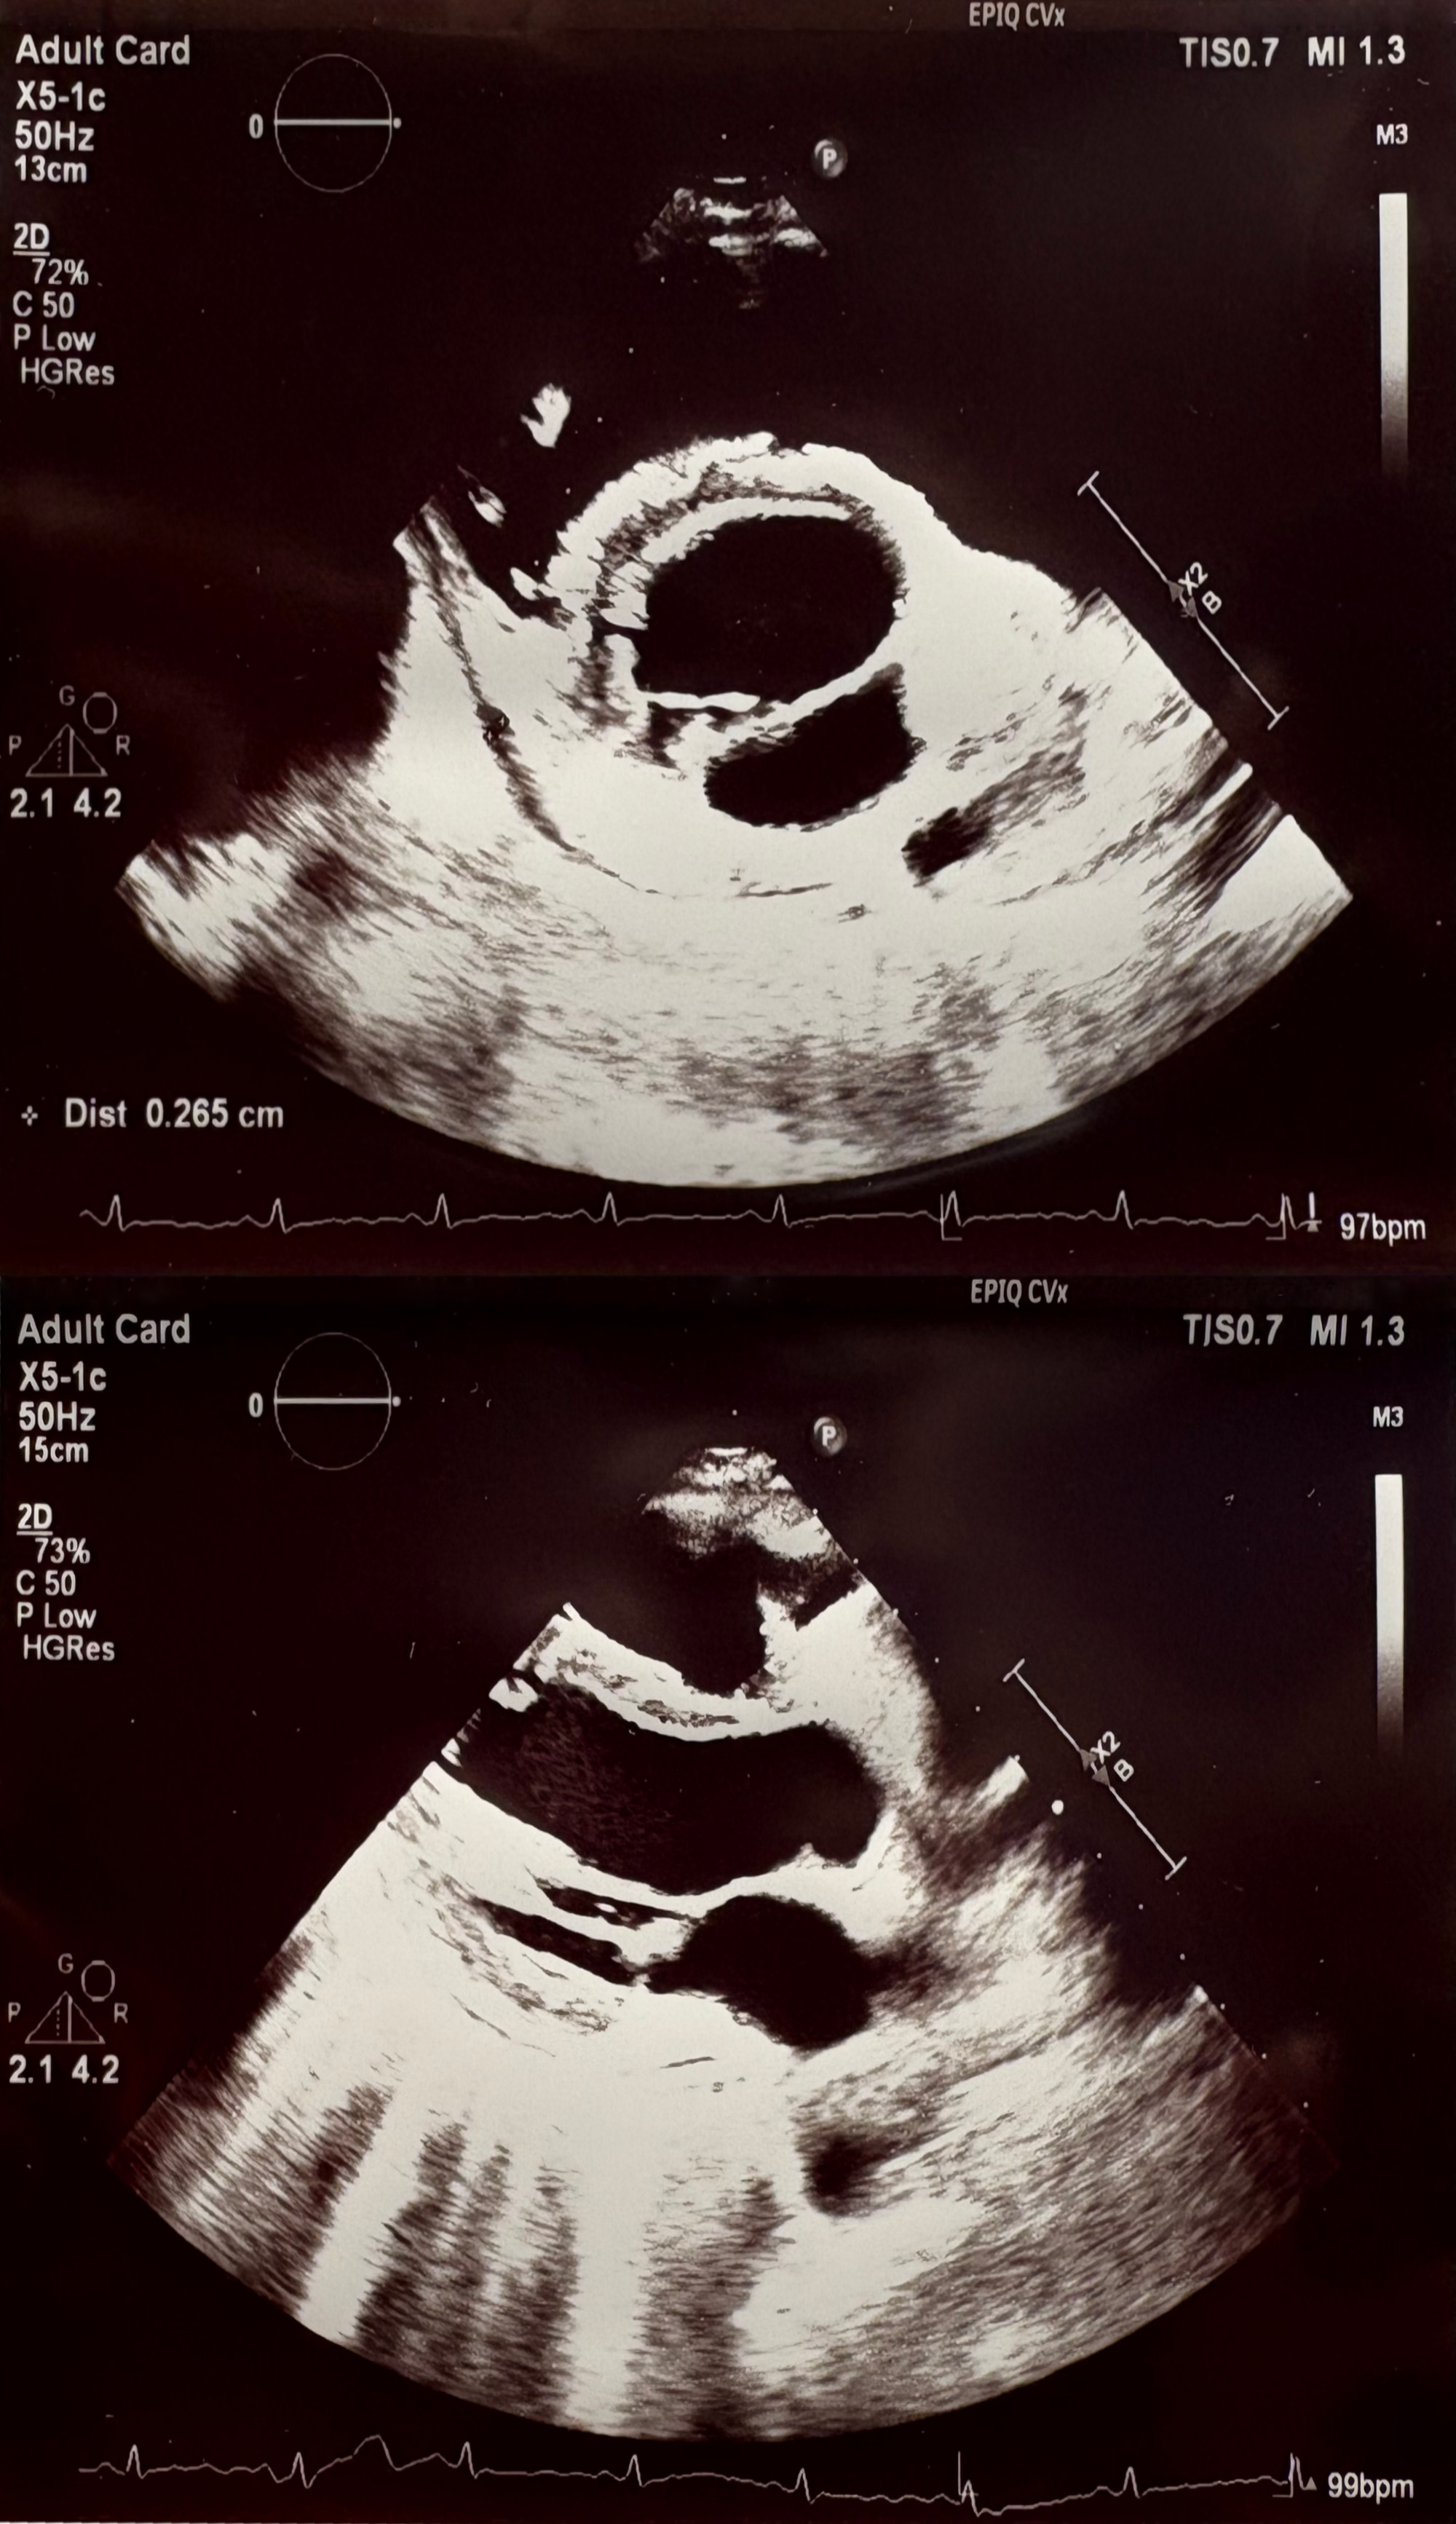

Non-contrast chest CT demonstrated diffuse miliary nodularity with focal consolidations in the right upper lobe segment S1 and left upper lobe segment S1, accompanied by hilar and mediastinal lymphadenopathy and a large pericardial effusion measuring up to 4 cm in thickness (Figures 2 and 3). A cardiology consultation was obtained. Screening transthoracic echocardiography (TTE) demonstrated a pericardial effusion measuring 3.8 cm, with evidence of cardiac tamponade. Although the patient remained hemodynamically stable, the large pericardial effusion with echocardiographic tamponade physiology warranted urgent echocardiography-guided pericardiocentesis to prevent progression to obstructive shock. The procedure reduced the effusion to 2.0 cm with resolution of tamponade, and a pericardial drain was left in situ. Pericardial fluid, sputum, urine, and stool samples were collected and tested for Mycobacterium tuberculosis (MTB) using smear microscopy, the Xpert MTB/RIF assay, and culture. MTB was detected by the Xpert MTB/RIF assay (positive for MTB DNA without rifampicin resistance) in multiple specimens, including sputum, pericardial fluid, and feces. Smear microscopy was negative in all samples except for scant acid-fast bacilli (AFB) detected in a single sputum specimen (Table 1).

No further drainage output was observed after several days. Repeat transthoracic echocardiography performed approximately one week later demonstrated well-defined pericardial layers and complete resolution of the effusion (Figure 4), with otherwise normal cardiac findings, and the drain was removed.